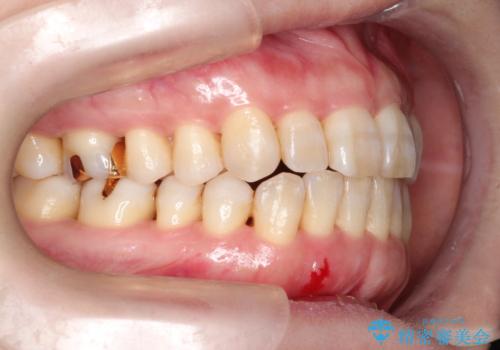

- 上下の前歯の開き(開咬)と上下前歯にガタつき(叢生)が見られます。

マウスピース矯正ではメカニクス的に開咬へのアプローチが容易です。

インビザラインの特色を生かした歯牙移動計画を作成し、非抜歯にて治療を行いました。